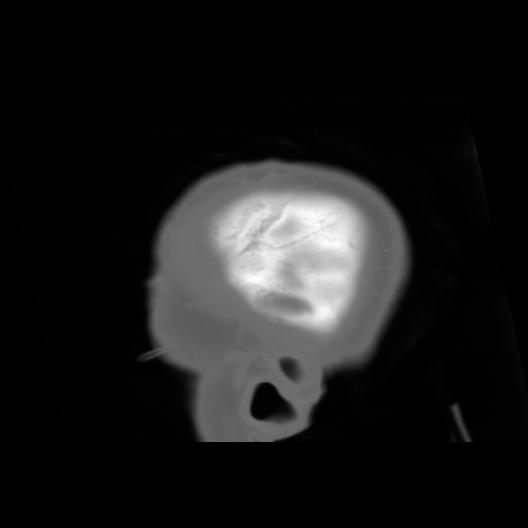

6 CEREBRO,,Sagittal,3.000,CEREBRO,Sagittal,